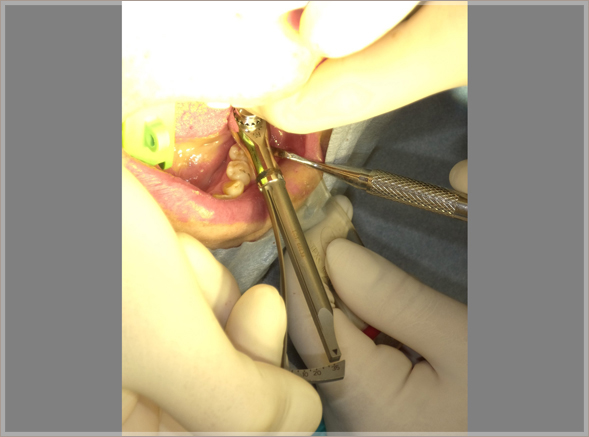

6.埋入ポジションを確認します

⑪埋入ポジションの確認

⑫埋入初期固定35N/cm(理想的)

7.角化歯肉の安定を考慮した縫合をします

⑬初期固定値が高いので1回法インプラント治療としてテンポラリーヒーリングアバットメントを埋入と同時にセット、角化歯肉の安定を考慮して縫合する。